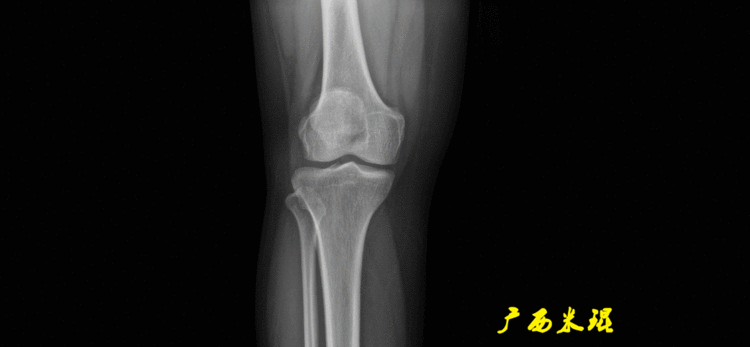

下肢力线及相关角度测量的前提是必须拍摄标准的站立位也就是负重位的下肢全长片。目前这样的照片都是放射科的技师在电脑上拼接出来的,大部分医院的DR都能够做到这一点。

患者直立于摄影架上,后背贴近摄影架,双手自然下垂,膝关节尽量伸直,足部与双肩同宽,要求投照时双髌骨朝正前方,通常患者双足尖应平行向前即可。

提醒一下大家,拍摄过程中应避免下肢的外旋和内旋。如果有一侧肢体短缩时,投照应当用脚垫垫高短缩肢体,使骨盆保持水平,这样下肢短缩测量才精确。如果有肢体旋转畸形时,还是以髌骨朝前为标准,虽然此时双足可能不能保持平行。

无论如何,拍摄出来的下肢全长片必须包含髋关节中心、膝关节中心及踝关节中心,否则对临床是无用的。有了一张下肢的全长照片,我们需要确定下肢关节的中心点,通过中心点画出下肢的各种轴线,然后利用轴线与关节线的相交得出各种所需要的角度。